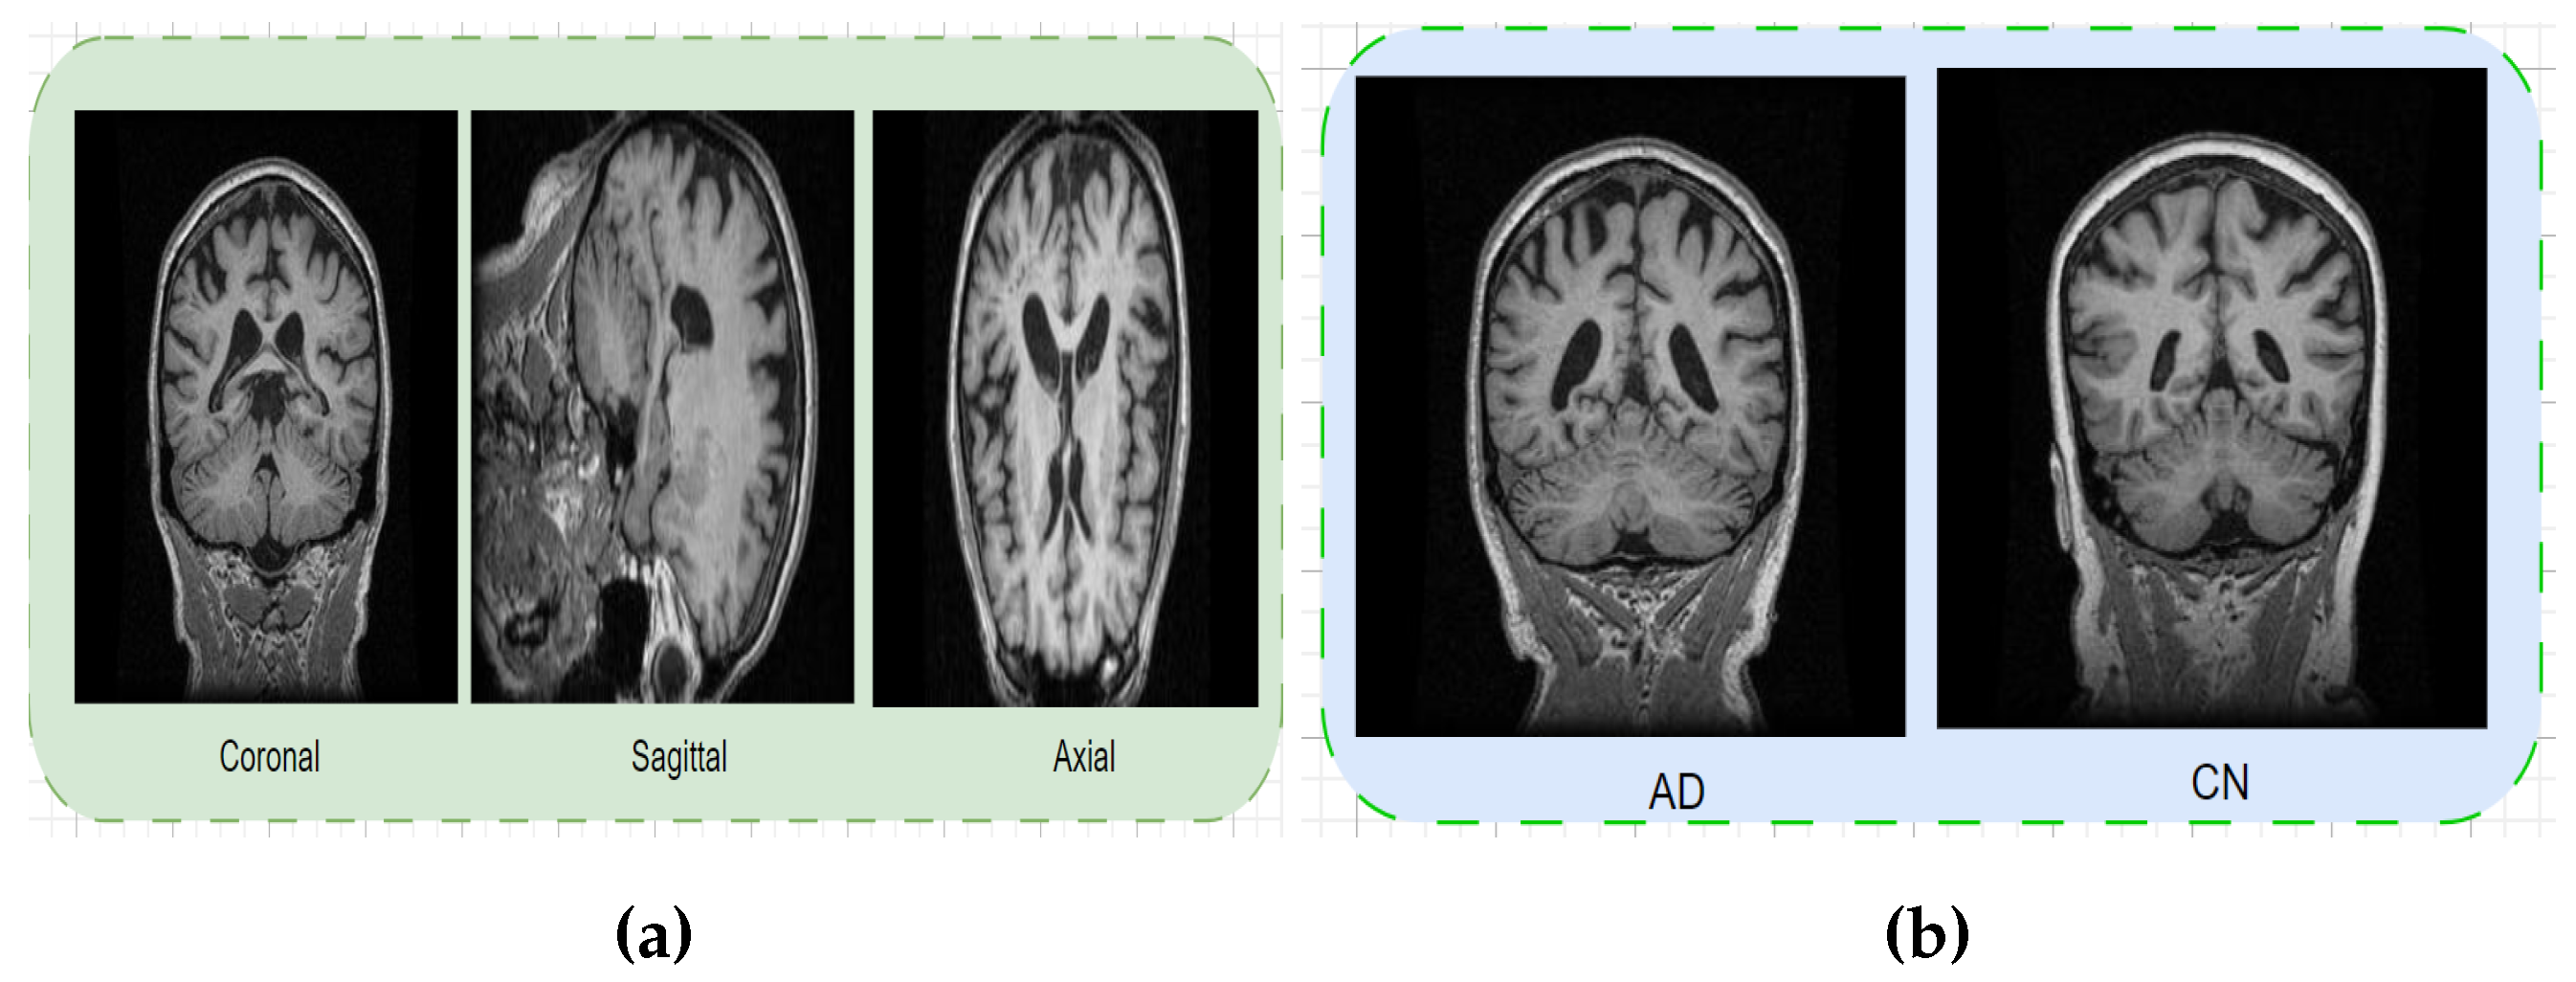

3. Dataset

3.1. MIRIAD Dataset

3.2. OASIS Kaggle Version Dataset

3.3. ADNI1: Complete 1Yr 1.5T